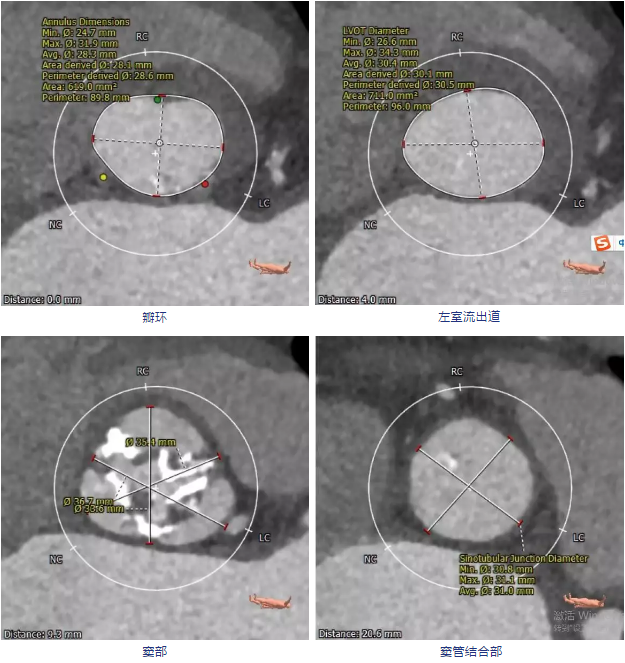

CT分析:

颈动脉入路输送系统模拟情况

建议术中球囊扩张确认冠脉风险,瓣膜型号推荐VenusA-Valve29号瓣膜,备选VenusA-Valve26号瓣膜。